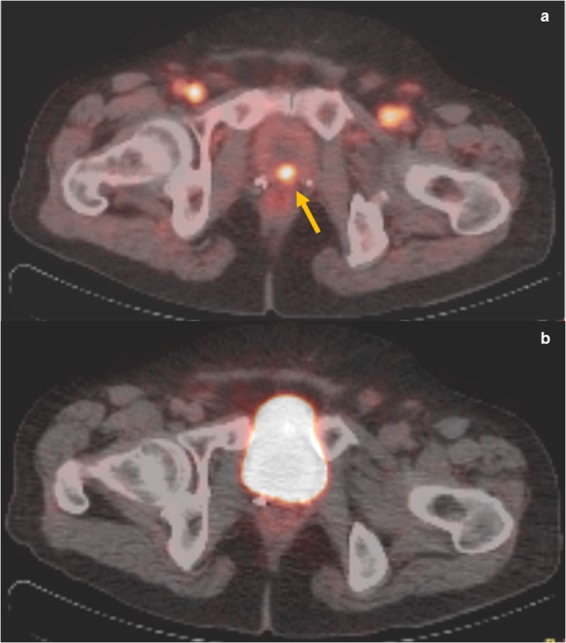

While the current standard of practice recommends imaging at 60 minutes post injection of 68 Ga-PSMA in PET/CT for prostate cancer, only a few studies have discussed the usefulness of imaging at an earlier time12. The rationale behind the use of early imaging is that cancer lesions show radiotracer uptake occurring before radiotracer accumulation in the urinary bladder, which may otherwise mask these lesions during the standard imaging at 60 minutes. Uprimny et al. found that bladder activity was absent within the first 3 minutes post injection, with all pathologic lesions showing radiotracer uptake at 3 minutes14. In a follow-up study performed using early imaging on 203 patients with biochemical recurrence, it was shown that early imaging significantly increased detection rate of local recurrence from 12.8% to 24.6% and that equivocal findings on imaging at 60 minutes significantly decreased from 15.8% to 4.5%15. Perveen et al. also prospectively studied 15 prostate cancer patients who underwent PSMA PET/CT, with all pathologic lesions showing early radiotracer uptake at 3 minutes and insignificant bladder activity as compared to standard imaging at 60 minutes. Similarly, in our study 8/167 (4.8%) had lesions seen on early imaging and masked by bladder activity on standard imaging. There was a statistically significant increase in detection rate from 64.0% using standard imaging to 68.3% when performing early imaging. Upon review of the images, the lesions that were missed on standard imaging were in the anterior aspect of the prostate or anterior aspect of the surgical bed in cases of prostatectomy. This demonstrates the importance of early imaging in enhancing target-to-background ratio of malignant prostatic lesions due to decreased radioactivity in the urinary bladder, thereby improving detection of lesions that would have been missed on standard imaging and thus changing the management of these patients. (Fig. 1).

Figure 1.

73 year old male presenting for prostate cancer staging. (a) The prostate gland shows a focus of increased activity in its center (arrow) with SUV max 4.2 at 3 minutes. Radiotracer activity in the inguinal vessels is also visible. Early PET/CT imaging helped detect tumor lesion that was obscured by radiotracer activity in the bladder on standard imaging at 60 minutes post-injection (b).